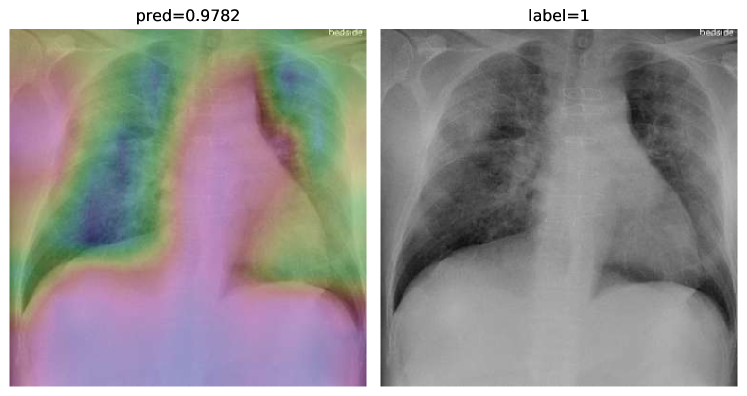

To overcome the aforementioned issues and force the model’s attention to the correct regions of interest (ROIs), we introduce the COVID-CXNet. Our model is initialized with the pretrained weights from CheXNet. A dataset of 3,628 images, 3,200 normal CXRs and 428 COVID-19 CXRs, are divided into 80% as training-set and 20% as test-set. Batch size is set to 16, rather than 32 in previous models, regarding memory constraints. Grad-CAMs of the COVID-CXNet for random images are plotted in Fig. 15.

Refer to caption

Figure 15: Grad-CAM visualization of the proposed model over sample cases

More Grad-CAMs are available in Appendix A. Heatmaps are more accurate than previous models, while an accuracy of 99.04% and an f-score of 0.96 are achieved. Table 3 is the confusion matrix of the proposed model.